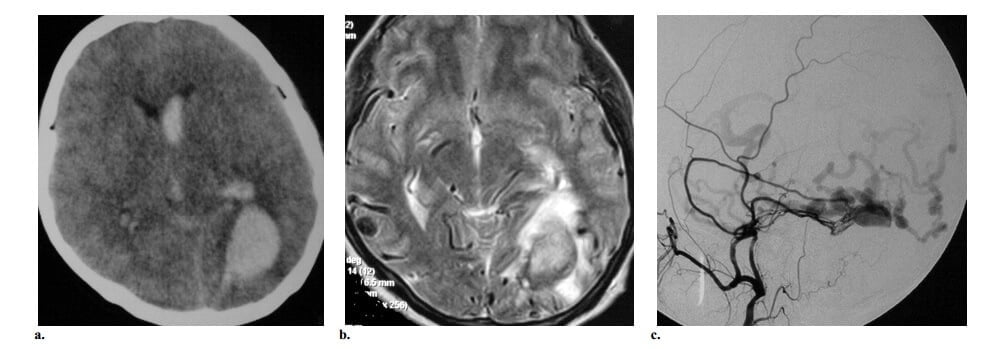

Điểm lưu ý: Các dấu hiệu CT và MRI gồm dãn tĩnh mạch vỏ não (một tình trạng được xem như là dạng giả viêm tĩnh mạch theo một số tác giả), có biểu hiện là các trúc dạng ống bắt thuốc bất thường hoặc flow void trong các rãnh vỏ não kèm không có nidus thực sự trong nhu mô não (hình 10).

Giảm đậm độ chất trắng trên CT hoặc tăng tín hiệu T2W trên MRI chứng tỏ xung huyết tĩnh mạch hoặc nhồi máu, cuối cùng có thể dẫn đến xuất huyết tĩnh mạch. Bắt quang khu trú các vùng nảy cũng có thể được quan sát thấy là một dấu hiệu của thiếu máu tĩnh mạch mạn tính. Đóng vôi dưới vỏ dạng đường cong có thể thấy trên CT ở bệnh nhân có hồi lưu tĩnh mạch vỏ não kéo dài, có thể do xung huyết tĩnh mạch mạn tính. Tuy nhiên, hình ảnh cắt lớp đơn độc thường không đủ để định vị AVF màng cứng. Các khảo sát động với MRA , CTA hoặc DSA (tham chiếu chuẩn) sẽ cho thấy lấp đầy tĩnh mạch sớm, sự đóng góp của các nhánh động mạch cảnh ngoài (hơn là các mạch máu màng mêm) và vị trí shunt. Bắt buộc phải điều trị cho AVF màng cứng do diễn tiến tự nhiên kém nếu không điều trị.

Hình 10: AVF màng cứng Borden type 2 ở phụ nữ 45 tuổi bị mất tri giác đột ngột. (a) Axial CT không cản quang thấy máu tụ thái dương chẩm trái với xuất huyết trong não thất. (b) Axial T2w cho thấy nhiều cấu trúc fliod voids mạch máu dọc theo các rãnh vỏ não của vùng chẩm hai bên. Có phù chất trắng với tăng tín hiệu trên T2W ở thùy chẩm trái. Không thấy nidus. (c) Chụp động mạch hàm trong trái cho thấy AVF màng cứng ở xoang ngang trái được cấp máu bởi động mạch màng não giữa trái. Ghi nhận có huyết khối đi kèm của phần gần và phần xa xoang ngang, tạo thành một “túi riêng biệt” và vì vậy gây ra dòng ngược từ shunt vào các tĩnh mạch vỏ não.